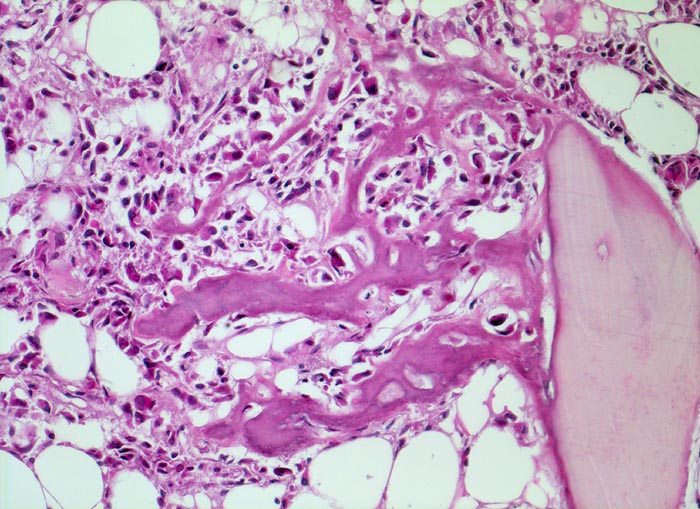

Osteosarkom

Knochen, Femur

Erhaltenes Spongiosabälkchen aus Lamellenknochen. Die Tumorzellen benutzen das ortsständige Knochengewebe als Leitschiene zum Anbau von Tumorosteoid.

16 jähriger Jugendlicher mit seit mehreren Wochen bestehenden belastungsunabhängigen Schmerzen im distalen Femur rechts oberhalb des Knies (Metaphyse). Im Röntgenbild irreguläre Verdichtung, zum Teil auch Aufhellung der ursprünglichen Knochenstruktur mit Zerstörung der Corticalis und spiculaartige (=sonnenstrahlenähnliche) Periostreaktion. Im Serum erhöhte alkalische Phosphatase.

Histologie

200